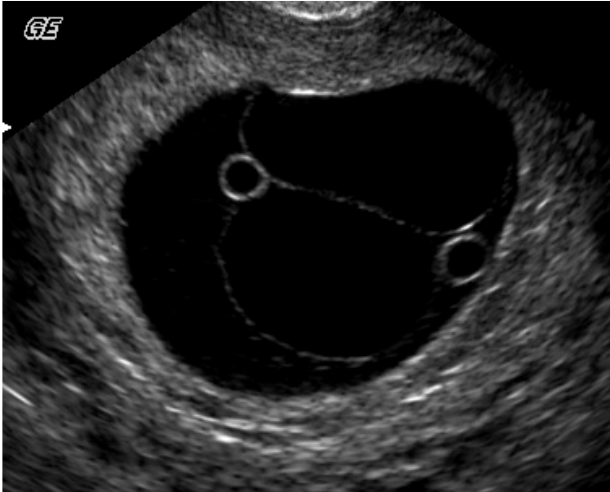

13

Q

A

dichorionic

diamniotic